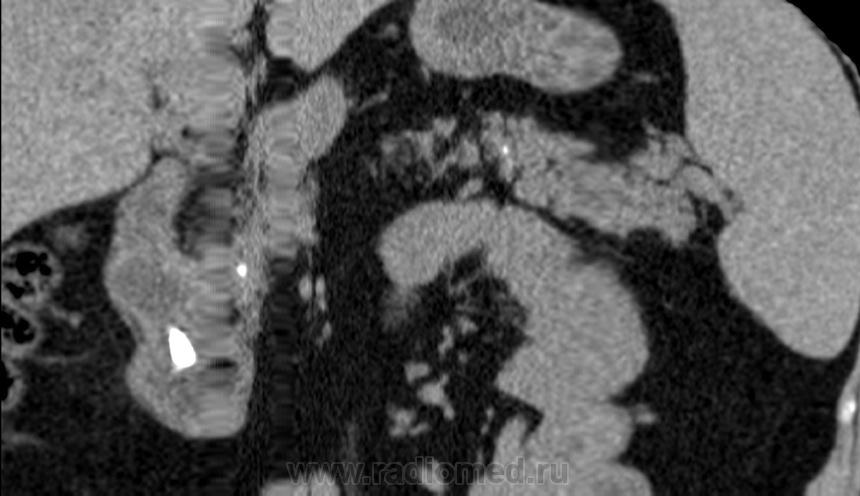

Итак пациент мужчина 34 года, в анамнезе - 16 эпизодов острого панкреатита (!). Пациенту была выполнена ЭРХПГ которая выявила наличие двух стриктур протока Вирсунга в области головки поджелудочной железы (доброкачественная стриктура Вирсунгова протока). На представленных мной изображениях определяется неоднородная структура поджелудочной железы с гиподенсными участками в области тела/хвоста и наличием паренхиматозных кальцификатов (b & c). Такая картина указывает на хронический панкреатит. В области головки визуализируется стент (a), установленный в Вирсунгов проток, с свободным концом в просвете 12-ти перстной кишки. Такое стояние стента является правильным. На данный момент, единственной адекватной терапией при доброкачественных стриктурах протока поджелудочной железы (и при некоторых опухолях исходящим из протока или обтурирующих его, когда невозможно выполнить резекцию) является эндоскопическое стентирование протока, что обеспечивает нормальный отток секрета поджелудочной в кишечник.

Верно. Об обструкции стента можно заподозрить только при наличии расширения протока дистальнее, или если пациент поступит с новым приступом острого панкреатита. В профилактических целях, стент периодически меняют.